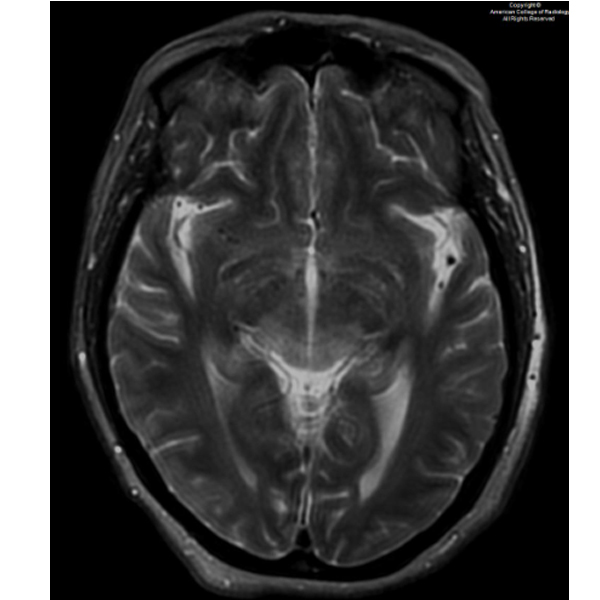

A 63-year-old female presents to the ED with right arm weakness, seizures, and confusion. #ACRCaseinPoint bit.ly/4lT0s1r